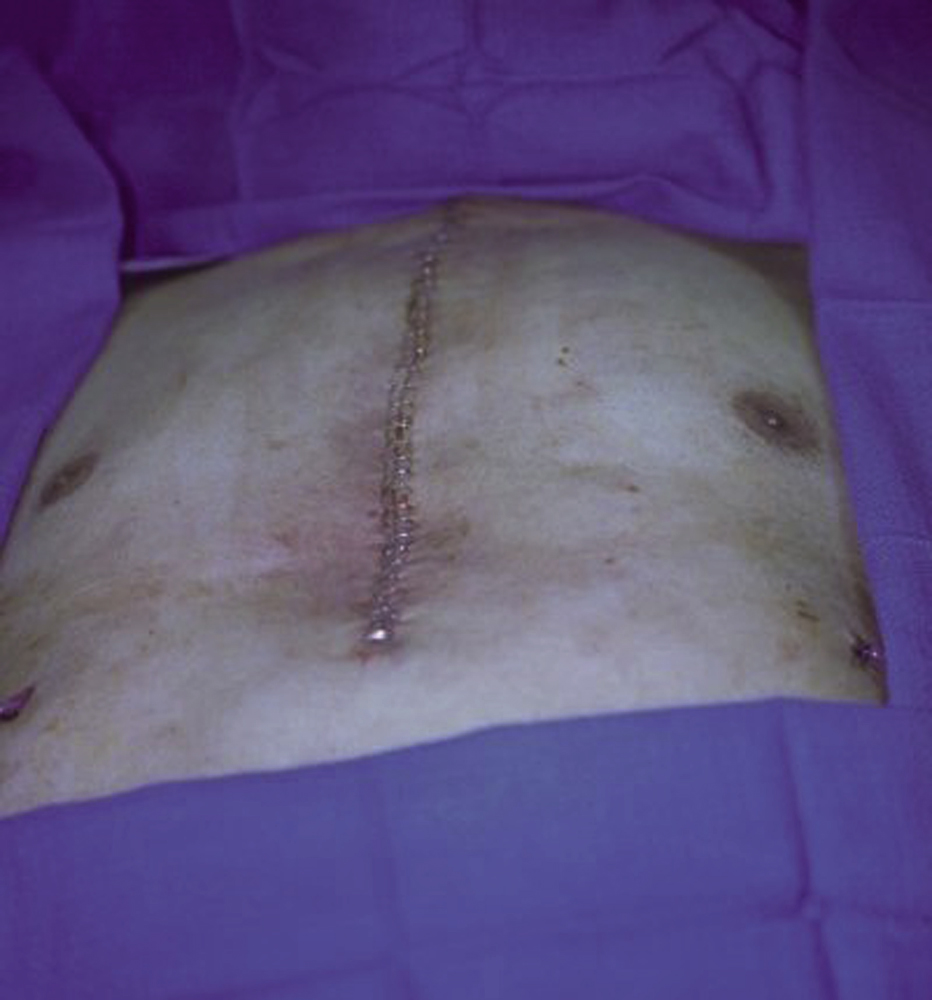

A 72-year-old Iranian male with multiple medical problems, including coronary artery disease, severe aortic valve stenosis, chronic occlusive pulmonary disease, and congestive heart failure, underwent coronary artery bypass grafting and aortic valve replacement as part of the preparation for a total gastrectomy because of a newly diagnosed large gastric carcinoma. He had a complicated postoperative course with prolonged treatment in the intensive care unit. He developed a dehiscence of the lower sternal wound and was urgently taken to the operating room by the cardiothoracic service for sternal wound debridement ( Fig. 21.1 ). All wires were removed during the initial debridement. The plastic surgery service was asked to provide soft tissue coverage to his sternal wound.

Under general anesthesia with the patient in a supine position, additional aggressive bony and soft tissue debridement was performed by both the cardiothoracic surgery service and the plastic surgery service. The wound was irrigated with warm antibiotic solution. At completion of the additional wound debridement, all wound edges appeared to be fresh and healthy ( Fig. 21.2 ).